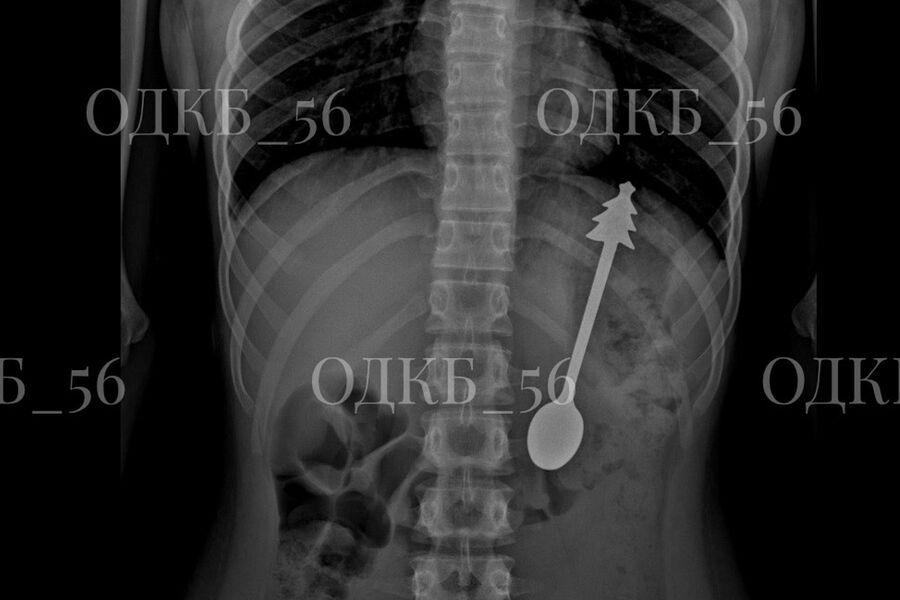

В Оренбургской области ребенок случайно проглотил 14-сантиметровую ложку

Врачи в Оренбургской области достали 14-сантиметровую ложку из желудка ребенка

Врачи извлекли 14-сантиметровую ложку из желудка ребенка в Оренбургской области. Об этом сообщила пресс-служба регионального министерства здравоохранения на странице в социальной сети «ВКонтакте».

По данным ведомства, несовершеннолетний случайно проглотил ложку, после чего его срочно госпитализировали. Бригада скорой помощи доставила ребенка в детскую больницу, где ему сделали рентген органов брюшной полости. В результате выяснилось, что инородное тело находится в желудке.

«В экстренном порядке проведено <...> эндоскопическое удаление инородного предмета — металлической ложки длиной 14 см. Постманипуляционный период протекал без осложнений», — говорится в заявлении.

Публикация дополнена фотографиями извлеченной из ребенка ложки. На кадрах видно, что на конце ручки столового прибора находится фигурка елки.